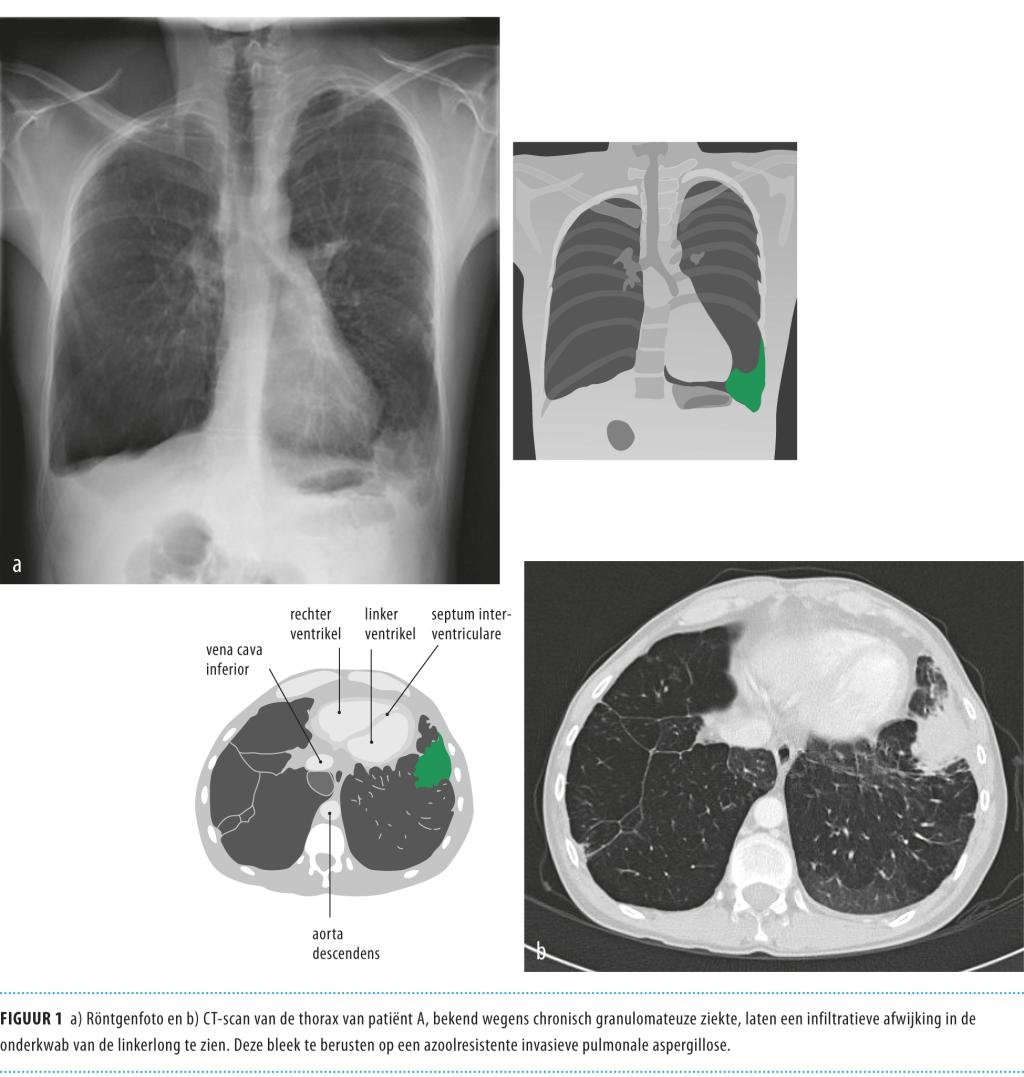

Aspergillus fumigatus is een saprofytaire schimmel die algemeen in de natuur voorkomt, maar die zijn niche vindt in met name organisch afval zoals compost. We ademen lucht in waarin de sporen (conidia) zich bevinden, en daarbij kunnen de sporen tot diep in de alveoli van de long terechtkomen. Bij gezonde mensen worden deze sporen opgeruimd door de alveolaire macrofagen, maar bij de immuungecompromitteerde gastheer kan Aspergillus een breed scala aan ziektebeelden veroorzaken. Invasieve aspergillose is een ernstige schimmelinfectie die dan ook primair voorkomt bij patiënten met verminderde weerstand, zoals patiënten die behandeld worden voor hematologische maligniteiten.

Bij de behandeling van Aspergillus-ziekten worden azolen in toenemende mate gebruikt. Daarbij gebruiken we itraconazol veelal bij niet-invasieve aandoeningen, zoals een aspergilloom, is voriconazol eerste keus voor invasieve aspergillose en is posaconazol effectief als profylactische behandeling bij hoogrisicopatiënten.